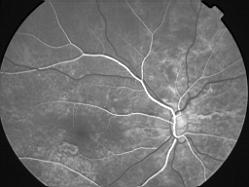

ASSOCIATION STRIES ANGIOIDES ET DYSROPHIE MACULAIRE RETICULEE

NEOVASCULARISATION